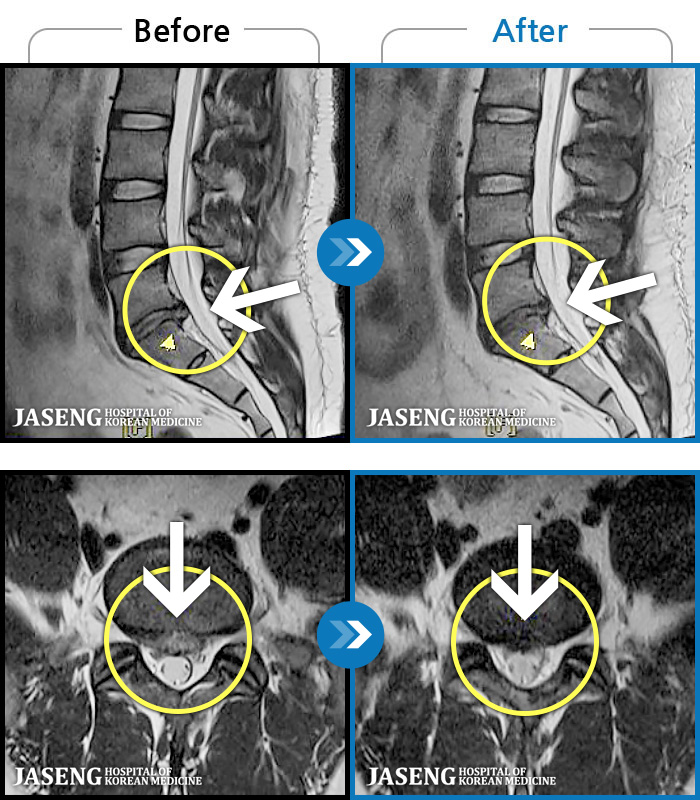

MRI ġ

1,237 MRI ũ ʸ Ȯϼ.

[Ȼ_㸮ũ] 㸮 ְ ٸ ȱⰡ .

[_㸮ũ] 㸮 , ٸ ̾ ϼ̽ϴ.

[õ_㸮ũ] ߲ 㸮 , ٷ

[ϻ_㸮ũ] ݺ ӵǸ ڼ ÿ ȭǴ ߵ ̻ ȣϴ ¿ϴ.

[ϻ_㸮ũ] ؽϰ ߰ ̴ · ϻȰ ¿ϴ.

[ؿ_㸮ũ] 㸮 ϰ

[_㸮ũ] 㸮 ߰ Ͽ ϼ̽ϴ.

[_㸮ũ] Ƹ ߱ ̾ ϼ̽ϴ.

[_㸮ũ] 㸮 ݱ , ٸ Ͽ ϼ̽ϴ.